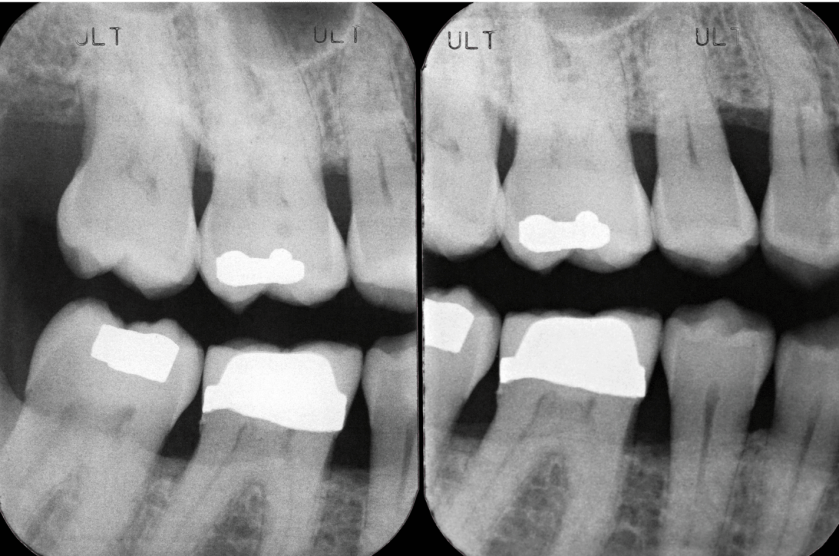

Más allá del cáncer, el tabaquismo tiene un impacto directo en la salud bucal. La periodontitis es la afección más frecuente en fumadores. Si no se detecta y trata a tiempo, puede provocar la pérdida de piezas dentales y una importante merma en la calidad de vida. Además, el tabaco favorece la sequedad bucal, incrementa el riesgo de caries, empeora el mal aliento, favorece infecciones como la candidiasis oral y puede provocar manchas en los dientes, fracaso de los implantes, pérdida de percepción del gusto y el olfato, así como dolor en las extracciones.